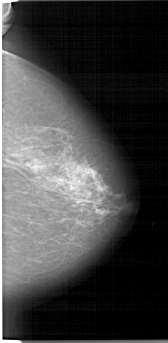

A_1335_1.RIGHT_MLO

RIGHT_CC LINES 6511 PIXELS_PER_LINE 3181 BITS_PER_PIXEL 12 RESOLUTION 43.5 NON_OVERLAY

RIGHT_MLO LINES 6391 PIXELS_PER_LINE 3211 BITS_PER_PIXEL 12 RESOLUTION 43.5 NON_OVERLAY